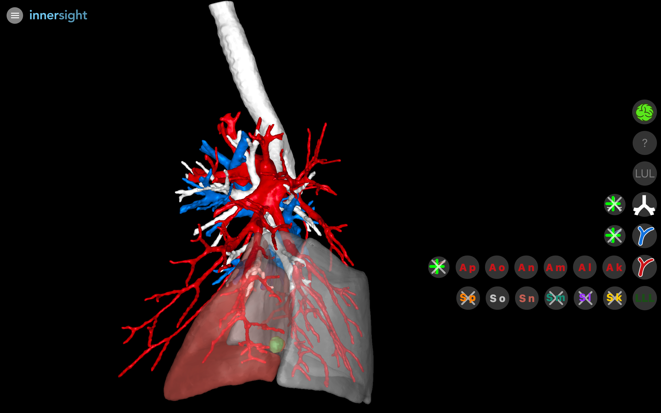

Une reconstruction 3D préopératoire est réalisée à partir du scanner thoracique non injecté de la patiente. Les images anonymisées du TDM au format DICOM sont téléchargées sur la plateforme Innersight (Karl Storz) puis traitées. La modélisation 3D est vérifiée puis accessible sous 48h sur plusieurs plateformes (ordinateur portable, tablette, smartphone).

La modélisation 3D intervient à deux étapes essentielles de la planification chirurgicale :

Détermination du type de segmentectomie à réaliser : Elle permet une localisation anatomique précise de la lésion au sein du parenchyme pulmonaire. À partir de cette localisation, le logiciel génère une marge de sécurité — correspondant à la quantité de tissu pulmonaire qu’il conviendrait de réséquer pour garantir une exérèse en zone saine, selon les standards appliqués en cas de carcinome bronchopulmonaire. L’analyse de ce modèle tridimensionnel permet alors d’évaluer la pertinence et la suffisance de la résection envisagée. Chez notre patiente, une lésion située à la base du segment latéro-basal (S9) du lobe inférieur gauche peut, après application d’une marge de sécurité de 2 cm, apparaître partiellement incluse dans le territoire du segment postéro-basal adjacent (S10). Dans ce cas, une segmentectomie S9 isolée serait insuffisante, et une bisegmentectomie S9-S10 serait indiquée afin d’assurer une exérèse complète avec marges satisfaisantes (Figure 3).

Analyse anatomique fine et navigation peropératoire : La modélisation 3D permet également une exploration séquentielle des structures vasculaires (artérielles et veineuses) et bronchiques. Cette analyse en couches successives favorise une planification chirurgicale précise. La connaissance préopératoire du trajet des artères et de leur territoire segmentaire permet d’anticiper les structures à préserver ou à sectionner, garantissant ainsi la conservation fonctionnelle des segments non concernés par la résection. Cette anticipation est essentielle pour optimiser la sécurité opératoire et la viabilité du parenchyme résiduel (Figure 4).